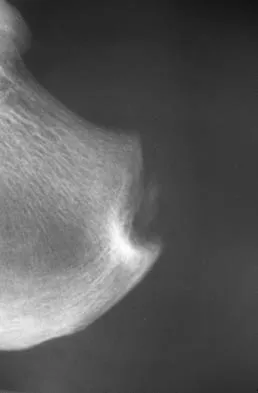

A 45-year-old man who has had recurrent pain and swelling of the left Achilles tendon insertion for the past 10 years reports that physical therapy and activity modification have provided relief in the past. He now has continued pain despite these efforts. He also reports occasional bouts of dysuria that he attributes to a history of prostatitis. He also notes recent eye irritation that he attributes to allergies. A lateral heel radiograph is shown in Figure 33. Which of the following laboratory studies would best aid in diagnosis?

Explanation